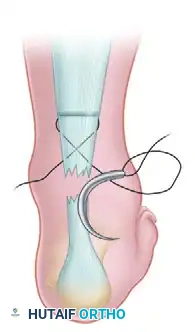

Step 2: Crisscross Suture Configuration

With a straight needle on each end of the inserted suture, crisscross the needles within the body of the tendon and puncture the skin just distal to the site of the tendon rupture. Enlarge the sites of needle puncture with a scalpel to prevent skin dimpling or necrosis. Pull the suture completely through the stab wounds and snug the suture within the proximal portion of the ruptured tendon to ensure a secure hold.

Image

Step 3: Distal Lateral Passage

With the lateral suture now threaded on a curved cutting needle, pass the suture back through the last stab wound to exit at about the midportion of the distal stump of the ruptured tendon on the lateral side. Enlarge the hole with a scalpel before pulling the suture through.